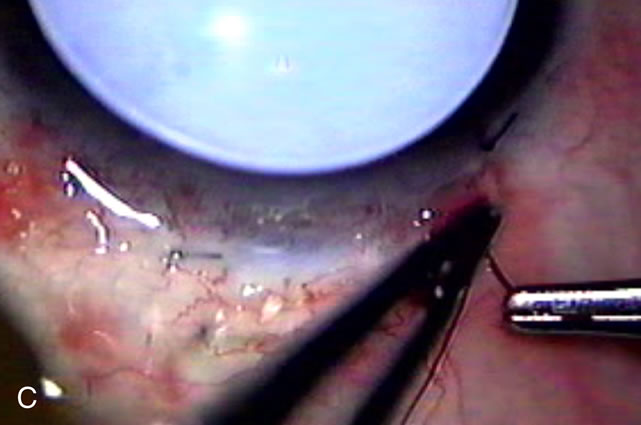

Cataract extraction by any technique performed in a patient with a pre-existing filter will have an effect on the previous filtering bleb.121–124 Bleb failure is more likely with ECCE compared with small-incision phacoemulsification.125 However, even patients undergoing topical anesthesia with clear corneal phacoemulsification and foldable IOL may experience bleb failure. One of three patients with a functioning filter and preoperative mean IOP of 12 mm Hg without antiglaucoma medications experiences bleb failure after lens extraction (Table 2). These patients require long-term drug therapy or bleb needling to control IOP. 126 Additional incisional glaucoma surgery may eventually be required in up to 10% of patients.127 Intraoperative iris manipulation may cause significant breakdown of the blood–aqueous barrier, resulting in inflammation that causes bleb failure. Even after uncomplicated clear corneal phacoemulsification, IOP may increase an average of 2 to 3 mm Hg due to bleb fibrosis.128 Approximately 20% of filtered patients require a long-term increase in glaucoma medications following uncomplicated clear corneal phacoemulsification with a foldable copolymer acrylic IOL129 (Fig. 3). In situations in which the bleb is not working at all, the eye will have a postoperative pressure spike that mimics that in the patient not having had a prior filtering procedure. In situations in which the bleb is marginal, the pressure spikes tend to be lower, and the final postoperative IOP tends to be around 50% higher than it was preoperatively. These patients require combined procedures in order to reestablish long-term filtration. In situations in which the bleb is very thin, polycystic, and associated with an IOP around 5 to 8 mm Hg on no antiglaucoma therapy; uncomplicated cataract extraction will have a minimal effect on the level of IOP. Patients with functioning glaucoma drainage implants usually have minimal long-term changes in IOP after uncomplicated cataract extraction.130

Fig. 3. Partial bleb failure following clear corneal phacoemulsification with foldable IOL. A. Preoperative bleb appearance prior to temporal lens extraction. Preoperative IOP was 12 mm Hg on no antiglaucoma medications. Time from 5-FU trabeculectomy surgery to lens extraction was one year. B. Bleb appearance 2 months after clear corneal cataract surgery with topical anesthesia. Following lens extraction, increased vascularity was noted along with decreased size of the filtering bleb. IOP increased to 20 mm Hg as early as 2 weeks after surgery, necessitating topical antiglaucoma therapy. C. High magnification view of bleb before lens extraction demonstrates diffuse pale bleb. D. High magnification view of bleb 2 months after surgery. There are vessels surrounding the nasal side of the bleb and the overall bleb size is smaller.